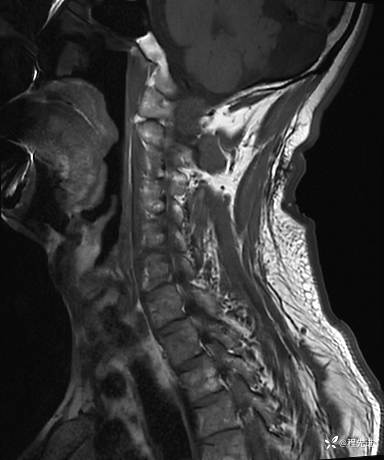

MRI平扫+增强:

T2: